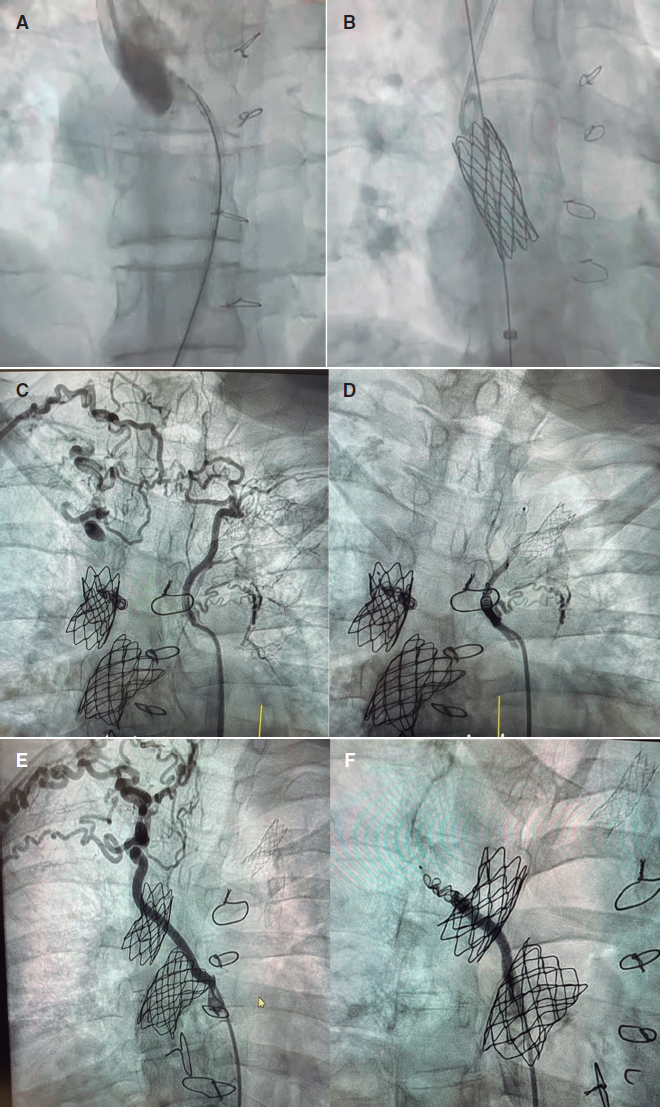

En nuestro medio, la experiencia desde 2015 de trabajo conjunto entre equipos pediátricos y de adultos ilustra bien esta filosofía. No se trata de compartir la sala de hemodinámica, sino de generar espacios comunes de discusión y decisión, en sesiones clínicas multidisciplinarias que permitan unificar criterios y diseñar estrategias personalizadas. Un buen ejemplo reciente, que refleja los beneficios de este trabajo conjunto, es un caso de optimización de Fontan con implante de stents y cierre de colaterales. La paciente, de 41 años, atendida en nuestro centro, presentaba una cardiopatía congénita compleja con corazón univentricular, concordancia auriculoventricular y discordancia ventriculoarterial, transposición completa de las grandes arterias, comunicación interventricular amplia, estenosis pulmonar e hipoplasia de ventrículo derecho. Se había sometido a numerosas cirugías y procedimientos previos (fístula de Blalock-Taussig a los 13 meses de edad, fístula sistémico-pulmonar a los 2 años y medio, derivación cavopulmonar superior tipo Glenn bidireccional a los 9 años, y derivación cavopulmonar inferior tipo Fontan extracardiaco a los 17 años), y presentaba una capacidad funcional disminuida y hepatopatía asociada al Fontan. Se le realizó un cateterismo cardiaco que confirmó la presencia de un tubo de Fontan muy calcificado y con una importante estenosis en su inserción a la rama pulmonar derecha. Inicialmente se procedió al tallaje con balón y luego al implante de un stent recubierto posdilatado con balón de 20 mm, con buen resultado. Por vía venosa yugular se confirmó una estenosis marcada en la anastomosis del Glenn a la rama derecha y se procedió al implante de un stent desnudo de 34 mm (figura 1A-B). Por vía arterial se realizó una aortografía en la que se observaron gruesas colaterales a ambos campos pulmonares, y se procedió a su cierre. La primera, hacia el lóbulo pulmonar superior derecho e izquierdo con tapón Amplatzer Vascular Plug 4 (Abbott Cardiovascular, Estados Unidos) y coils; la segunda, hacia el lóbulo superior derecho con tapón Amplatzer Vascular Plug 4 y coils (figura 1C-F). Este caso refleja muy bien la sinergia entre los hemodinamistas pediátricos y de adultos para completar el tratamiento.

Figura 1. Optimización de Fontan. A: estenosis en la anastomosis del Glenn con la rama derecha. B: stent desnudo implantado en dicha estenosis. C: gruesa colateral aortopulmonar que va hacia los lóbulos pulmonares superiores derecho e izquierdo. D: cierre de dicha colateral. E: gruesa colateral aortopulmonar que va hacia el lóbulo superior derecho. F: cierre de la colateral.